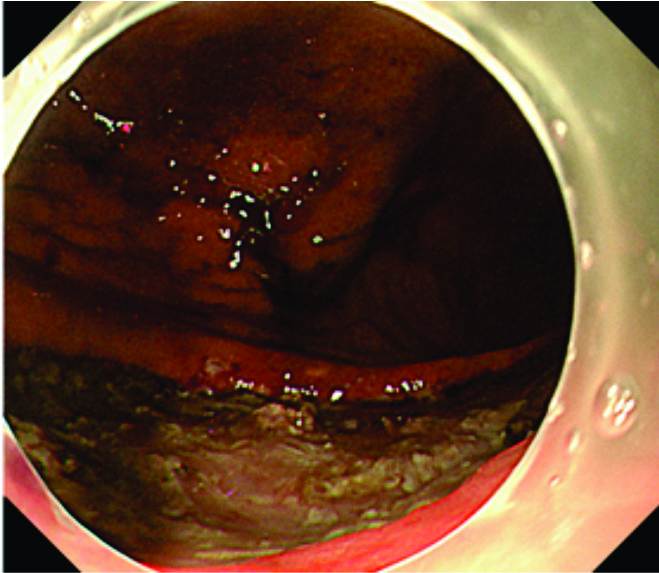

Resection specimen